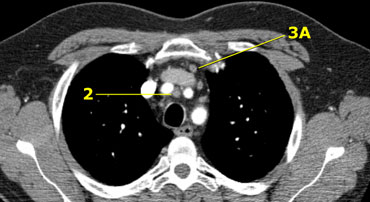

Axial CT anatomy

Images by Dr. Aurelia Fairise of the Institut de Cancérologie de Lorraine in Nancy.

1. Thượng đòn

2R. Cạnh trên phải khí quản

2L. Cạnh trên trái khí quản

3A. Trước mạch máu

3P. Sau khí quản

4R. Cạnh dưới phải khí quản

4L. Cạnh dưới trái khí quản

5. Dưới quai động mạch chủ

6. Cạnh động mạch chủ

7. Dưới carina

8. Cạnh thực quản

9. Trong dây chằng phổi

10. Rốn phổi

11. Gian thùy phổi

Kéo dài từ bờ trên trái của khí quản.

Bờ trên: bờ trên của cán ức.

Bờ dưới: chỗ giao nhau của tĩnh mạch vô danh với khí quản.

3A. Trước mạch máu (Pre-vascular)

Những hạch này nằm ở phía trước các mạch máu, không nằm cạnh khí quản như nhóm 2.